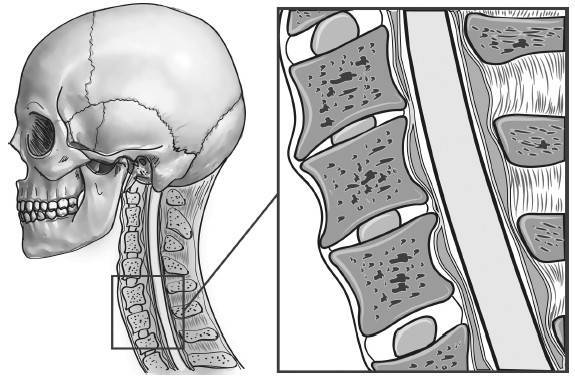

Причем, опять же, рост этого горбика она объясняет исключительно «солями» – остеохондрозом – и не связывает с изменившейся статикой своего позвоночника. В норме позвоночник, как известно, не должен быть прямым, как палка, а иметь физиологические изгибы. В частности, шейный отдел, состоящий из 7 позвонков, в норме должен быть чуть прогнутым внутрь (рис. 13).

Рис. 13. Нормальная статика шейного отдела

Из-за того что с возрастом диски между позвонками уплощаются, длина шеи укорачивается, и частенько весьма значительно (рис. 14).

Рис. 14. Шейный отдел позвоночника